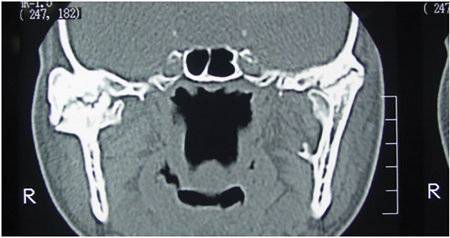

On an X-ray, the dentigerous cyst appears as a well-defined radiolucent area around the crown of the impacted tooth. It’s important to note that dentigerous cysts often don’t cause any symptoms and are found incidentally. However, if they grow in size or become infected, they can lead to swelling, pain, or displacement of nearby teeth.

Treatment for dentigerous cysts usually involves surgical removal or marsupialization, which is a procedure that creates a surgical opening to allow drainage and shrinkage of the cyst. This is done to prevent complications and facilitate the eruption of the impacted tooth.